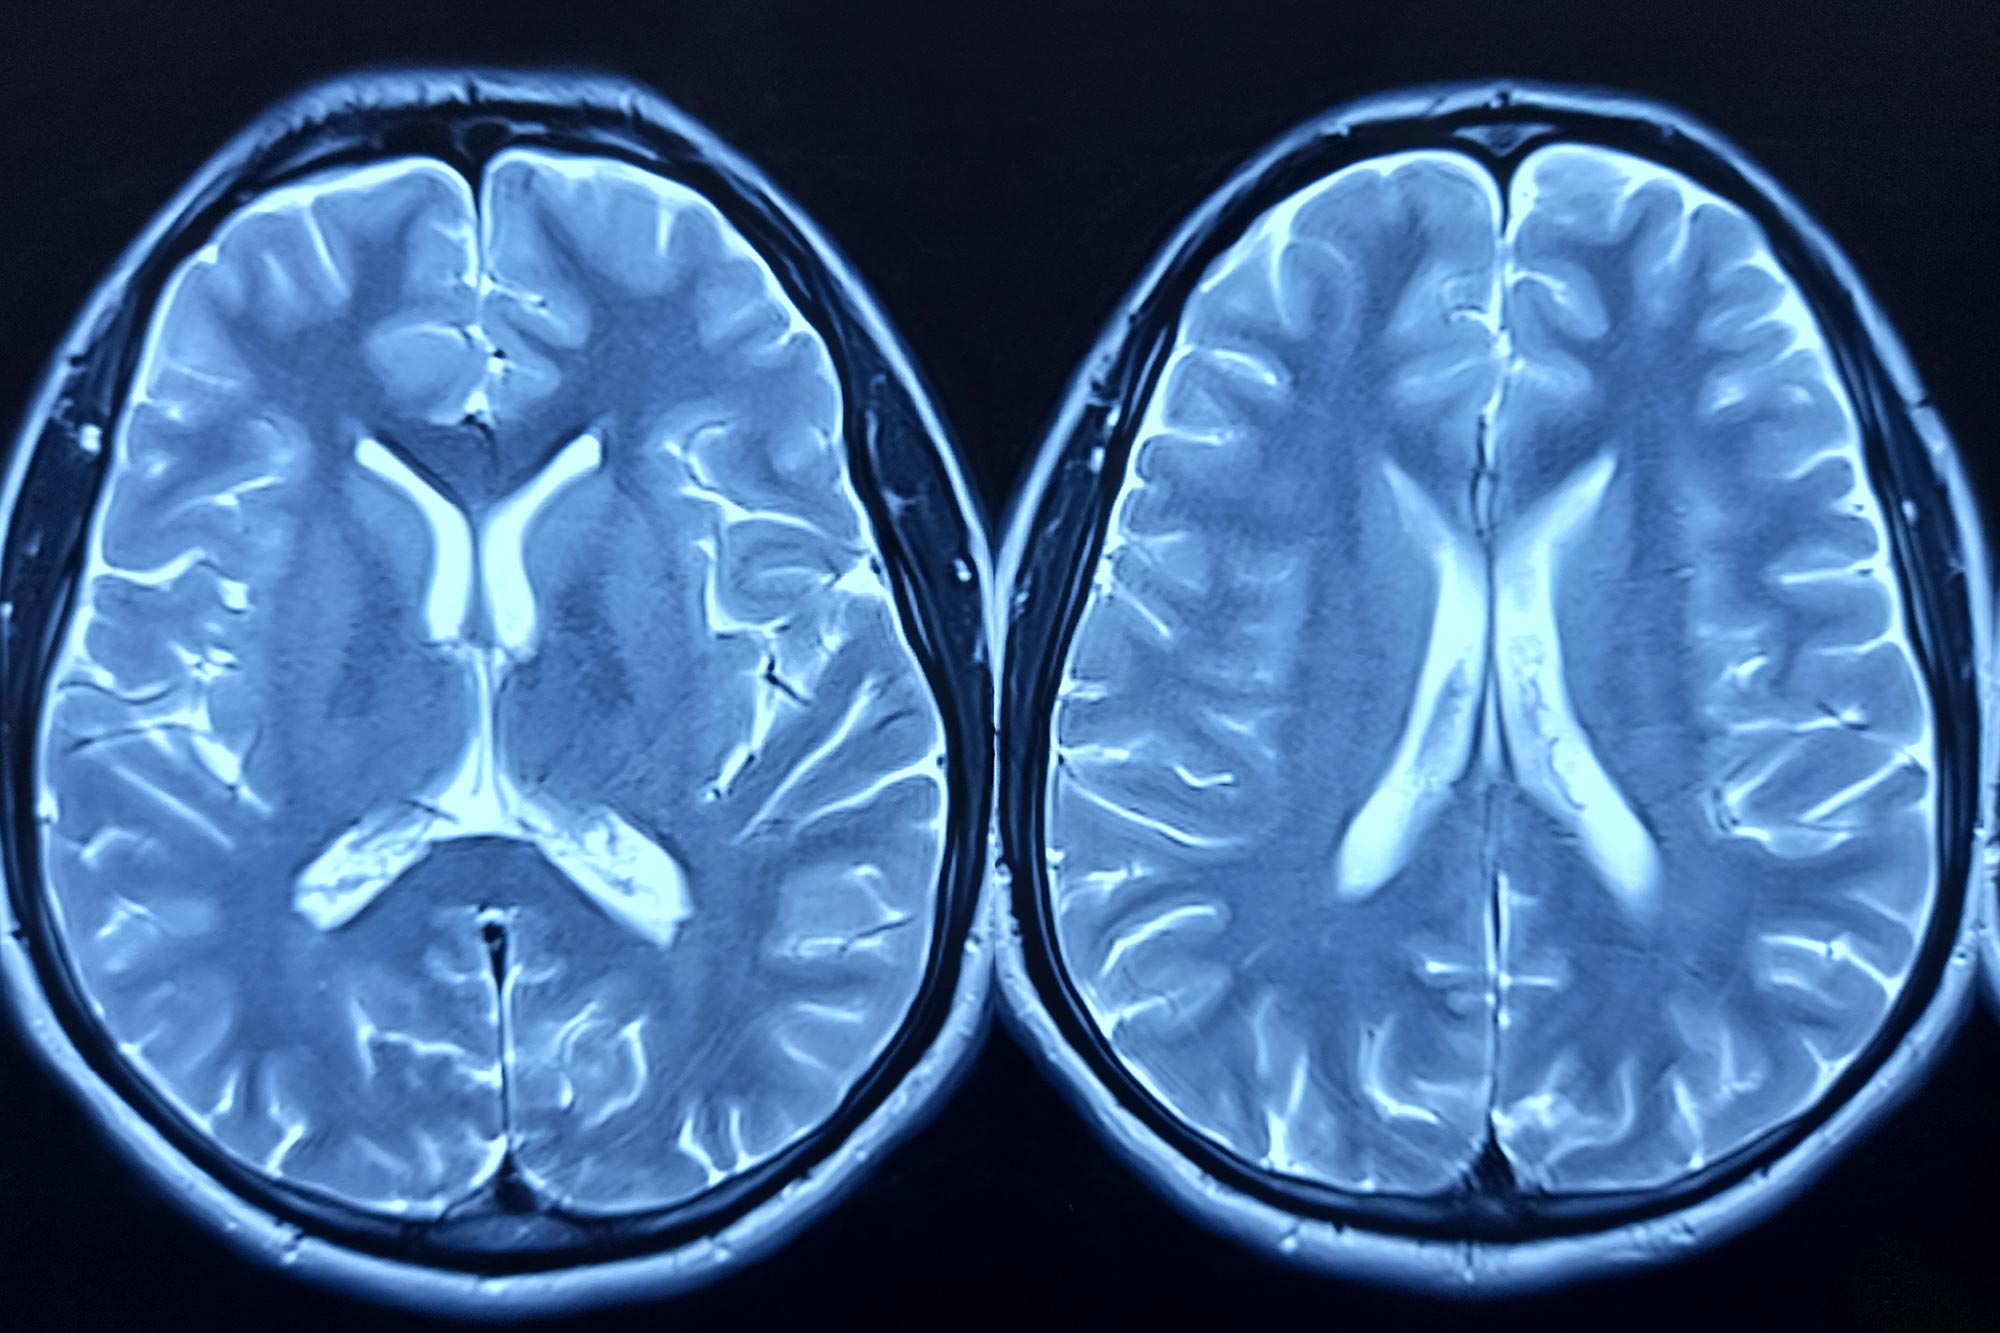

A new study finds autism symptom severity, not diagnostic labels, maps to shared brain-network connectivity and gene-expression patterns linked to autism and ADHD, suggesting a common biology across neurodevelopmental conditions.